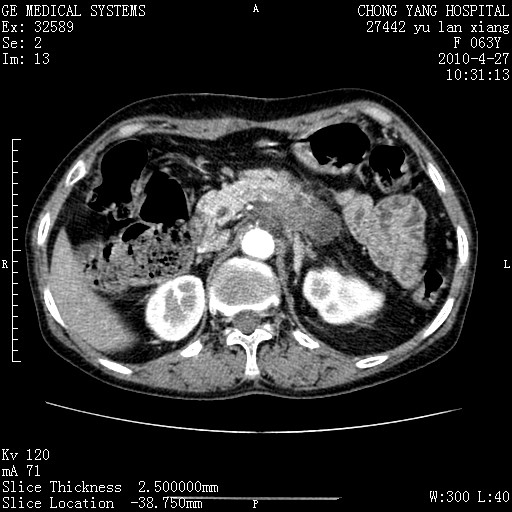

标题: CT26066:F63Y 上腹正中压痛半月,CA199:7400u/ml,MR示胰腺炎伴 [打印本页]

胰腺癌侵犯腹腔动脉干-分支、胃壁、左侧膈肌伴胰周及腹膜后淋巴结转移、胆囊切除术后。

胰腺癌侵犯腹腔动脉干-分支、胃壁、左侧膈肌伴胰周及腹膜后淋巴结转移、胆囊未显影。